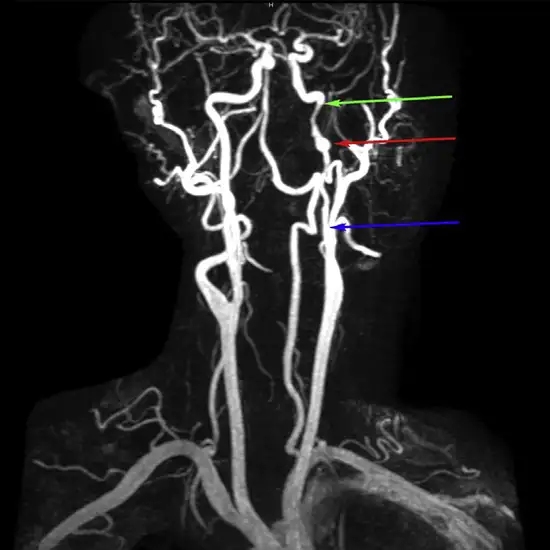

Carotid angiography also called an angiogram, is a test that helps find out if you have a disease in your carotid arteries. Doctors do this test to see how blood flows through the large arteries in your neck.

Carotid angiography detects blockages in the arteries that carry blood from the heart to the head and brain. Providers inject contrast dye with a catheter to see blocked arteries.